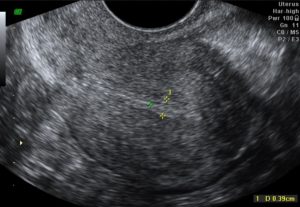

Диагностирование патологии

При обращении за профессиональной помощью пациентка отправляется на консультацию к гинекологу. Врач проводит сбор основных данных, внося их в историю болезни. После выставления предварительного диагноза больная направляется на ультразвуковое обследование матки, сдает анализы на показатели гормонального фона, клиническое исследование мочи и крови.

Если было диагностировано бесплодие или прерывание беременности на ранних сроках, особенно после перенесённых заболеваний или гинекологических процедур, обязательно проводить мониторинг состояния эндометрия. Делается это с помощью УЗИ матки.

Наиболее эффективными диагностическими мерами при данной патологии считаются:

- Ультразвуковая сонография – при нормальной ситуации обнаруживается трехслойная клеточная структура, которая позволяет забеременеть (хотя вероятность не превышает 25%), даже если слизистая оболочка истощена (меньше 5 мм) и понизить вероятность выкидыша. Когда эхопризнаков трехслойной формации нет, беременность не наступает.

После изучения общих симптомов пациентке назначают:

- УЗИ матки, которое проводят несколько раз на разных фазах цикла;

- УЗИ органов малого таза;